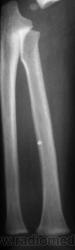

Травма.   Ребенок направлен на рентгенографию костей предплечья и локтевого сустава.

Поднадкостничный перелом в/3 лучевой кости.

Я думаю,что в с/3 нет перелома,скорее всего полосы просветления-тени сосудистых каналов,может я и не права.